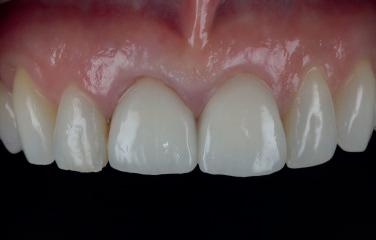

Case 1: Anterior tooth restoration with composite

Case 2: Posterior tooth restoration with composite

Restorations with BEAUTIFIL II LS, BEAUTIFIL Flow Plus X and OneGloss by Erik-Jan Muts, M.Sc., Netherlands